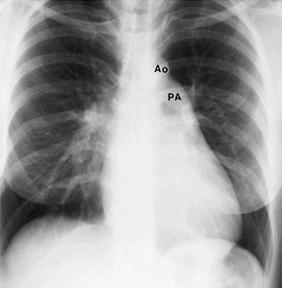

Rx cord-pulmon: circulatie pulmonara 'incarcata' cu ramurile AP dilatate in hiluri si extremitati 'retezate' avind periferie mult mai clara decat normal, bombare a conului arterei pulmonare, semne de hipertrofie VD

Imagine radiologica de HTP primara

Imagine Rx. de profil cu HVD Aspect CT de HTP primara